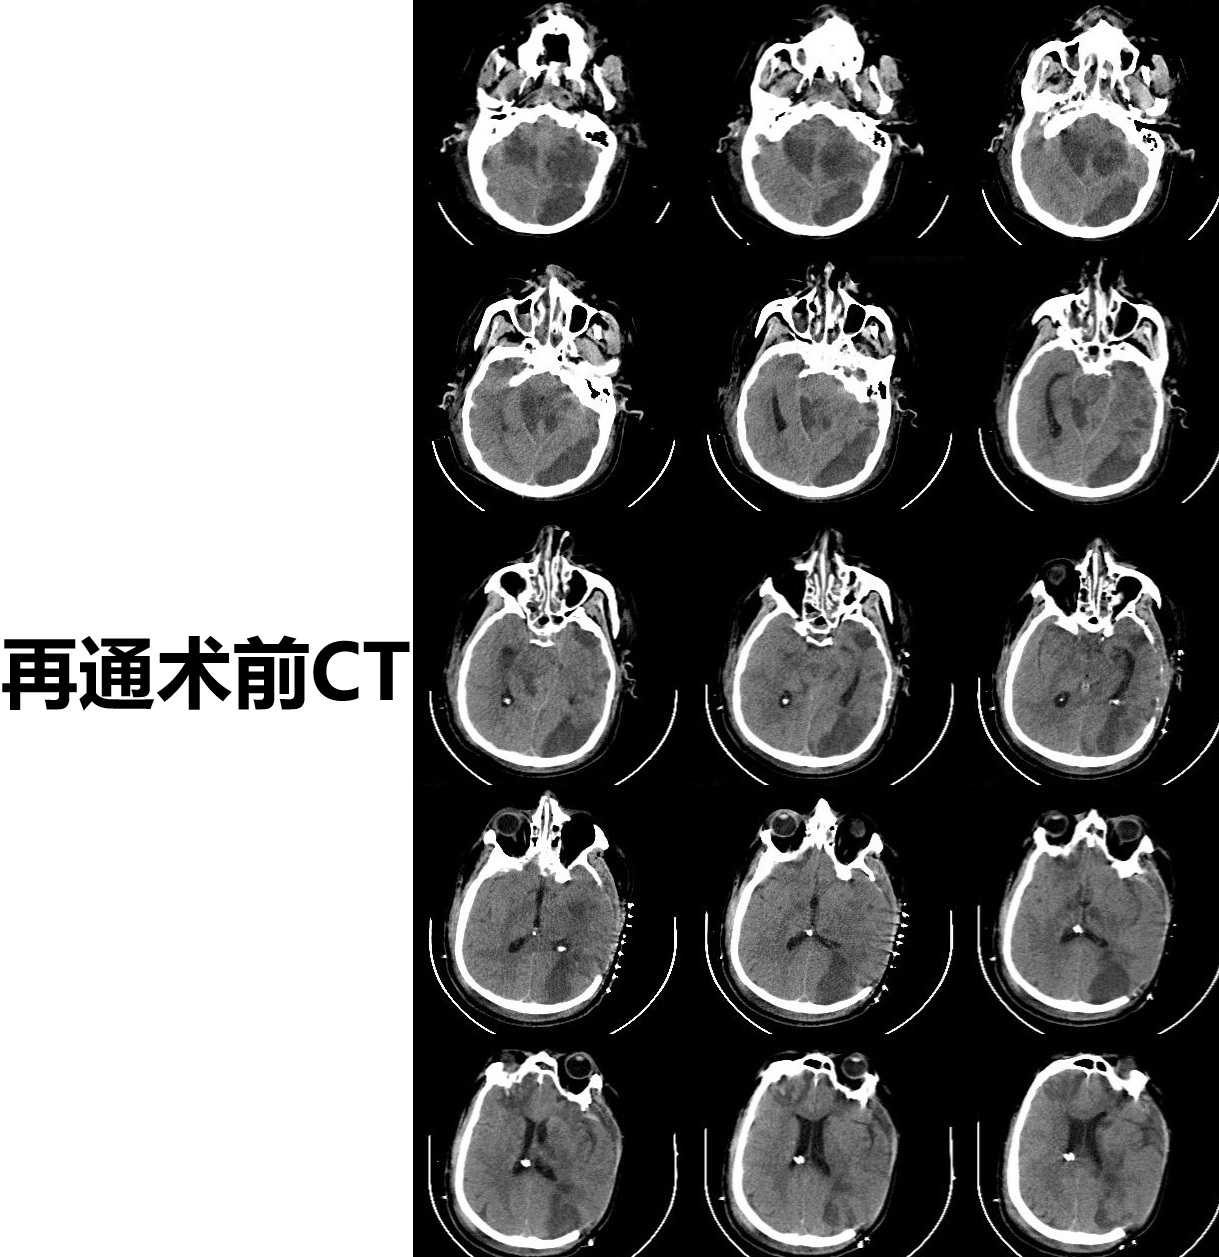

患者为机器碾压导致的复合伤,考虑外伤诱发左侧颈总动脉闭塞,导致多发脑梗死,予以去骨瓣减压手术,病情平稳后,查DSA提示:左侧颈总动脉闭塞,闭塞段位于颈2椎体至颈6椎体之间。和家属充分沟通后,行显微左侧颈动脉开通手术,手术顺利,术后患者症状明显好转,特此分享。